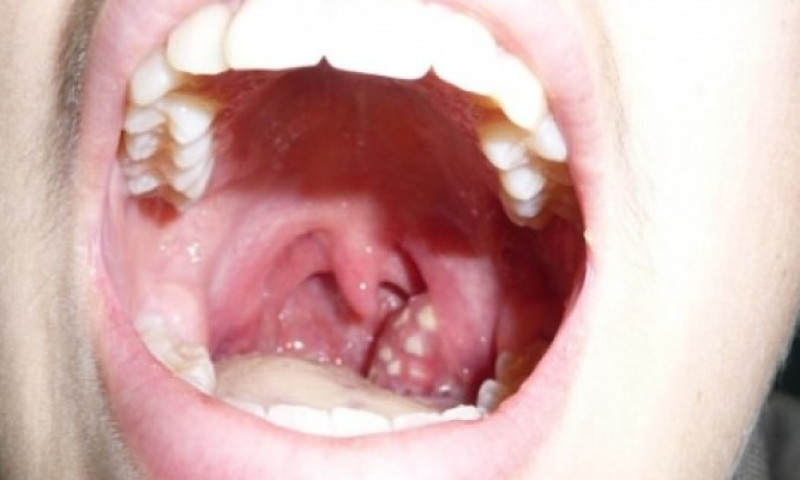

बारम्बार देखिएको टन्सिल फाल्नु नै राम्रो

यदि तपाईंलाई एक–दुईपटक मात्र टन्सिलको समस्या देखिएको छ भने चिकित्सकको सल्लाह लिएर घरमै सामान्य एन्टिबायोटिक खाँदा हुन्छ । तर, खाना निल्न र श्वास फेर्न नै गाह्रो भएको छ भने अस्पतालमा बसेर इन्जेक्सनबाट औषधि लगाउनुपर्ने हुन्छ । जटिल खालको र धेरैपटक दोहोरिएको छ वा दुई वर्षदेखि पटक–पटक देखिइरहेको छ भने अप्रेसन गरेर टन्सिल निकाल्नु नै राम्रो हुन्छ । त्यसरी निकालिसकेपछि पुनः टन्सिल हुने सम्भावना हुँदैन । अन्य कारणले भने घाँटी दुख्नसक्छ । टन्सिल निकालेपछि अन्य कुरालाई असर पर्दैन । कतिपय मानिस स्वर भासिन्छ भन्छन्, तर त्यो सत्य होइन । टन्सिल बिग्रिएर भासिएको स्वर निको भएपछि आफैँ ठीक हुन्छ ।